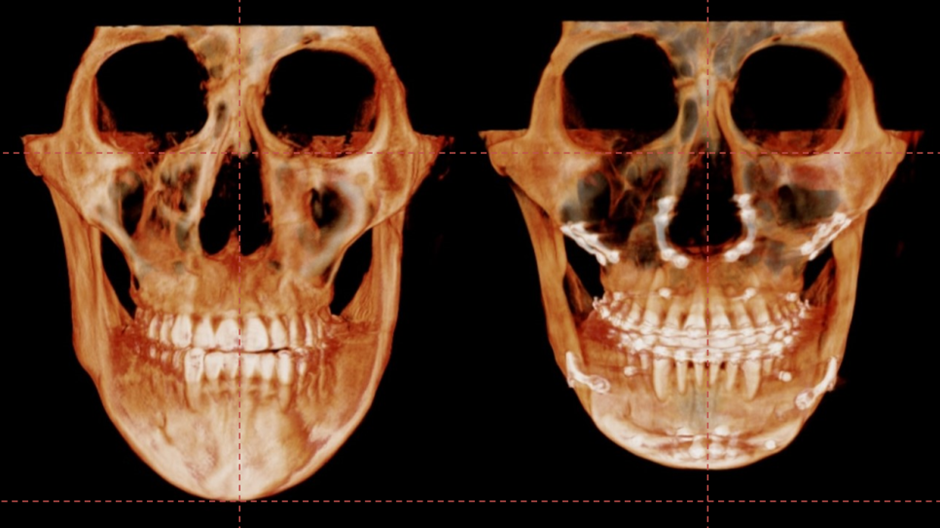

이번에 소개드릴 환자는 골격성 3급 부정교합을 가진 환자입니다.

주걱턱, 긴얼굴, 비대칭을 해결하고자 저희 병원에 내원하셨고

양악수술과 윤곽수술을 병행하기로 하였습니다.

수술 3개월이 경과한 시점에 촬영한 CT입니다.

이식한 뼈는 자연스럽게 리모델링 되면서

거의 흡수 없이 잘 생착 된 상태로 회복하였습니다.